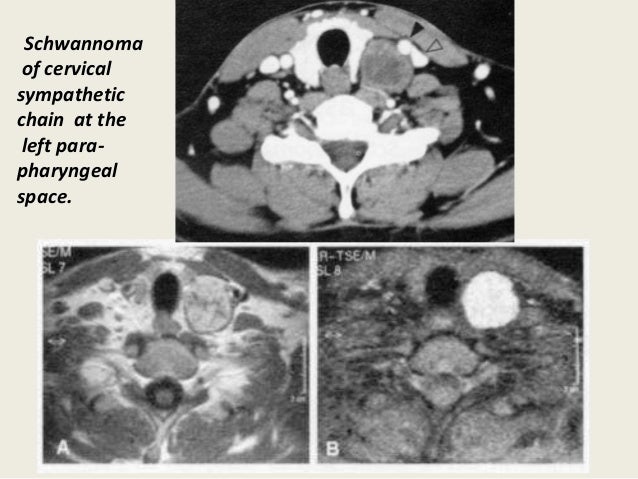

Presentation2, radiological imaging of neck schwannoma.

Presentation2, radiological imaging of neck schwannoma. from image.slidesharecdn.com